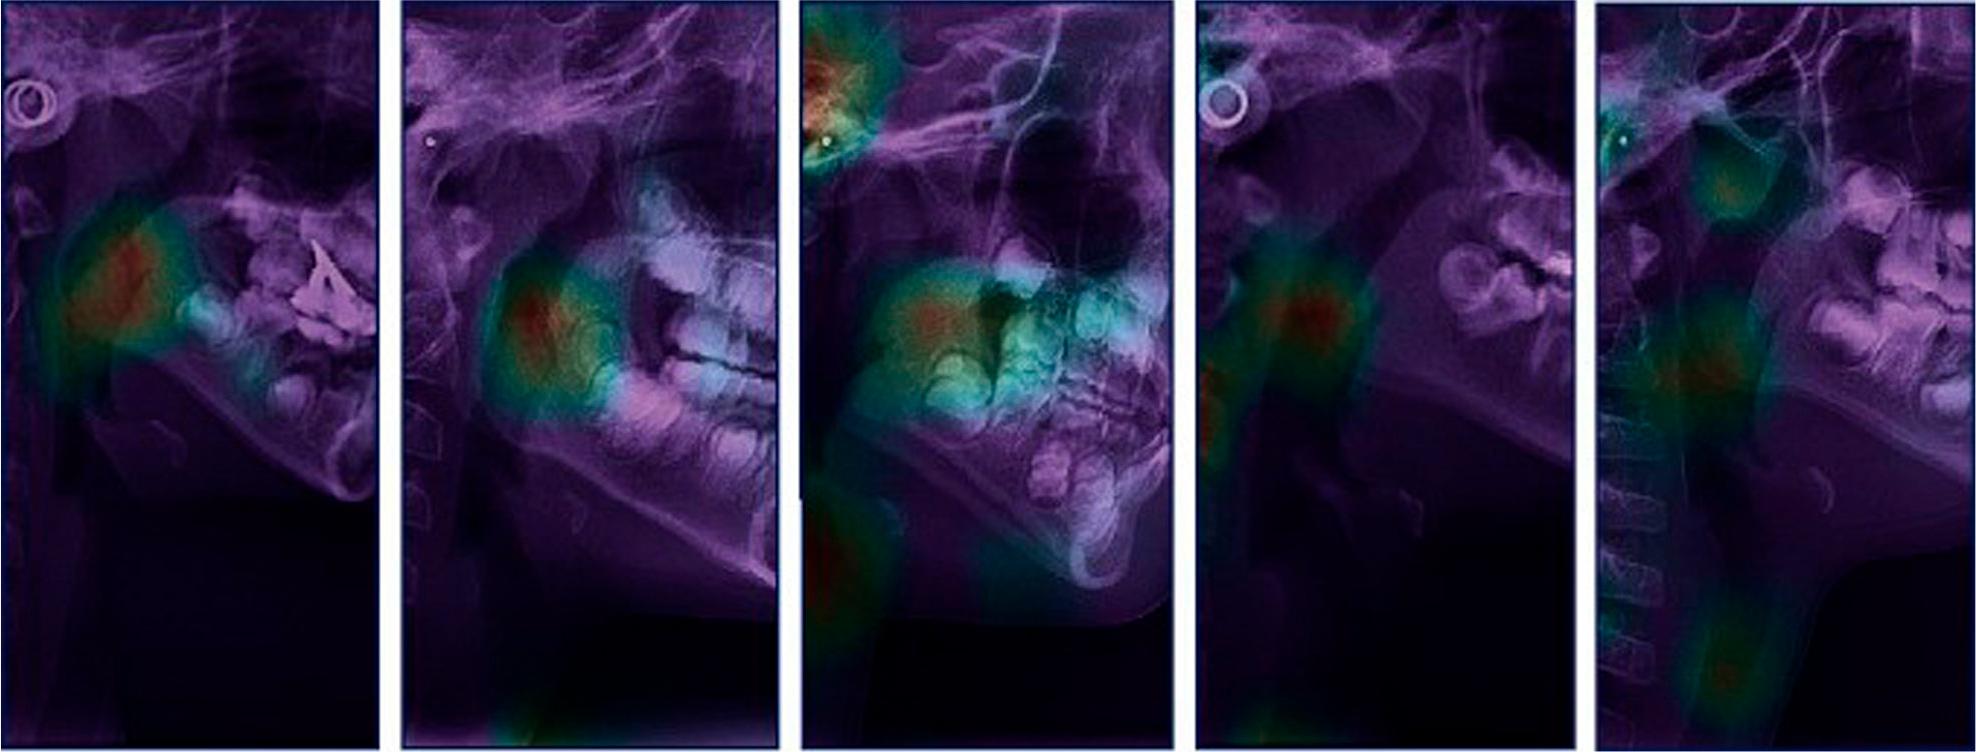

Figure 2.